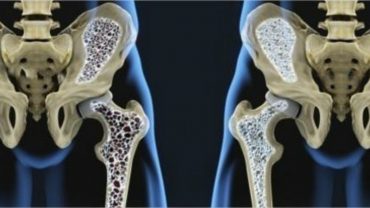

Las anemia, una de las consecuencias al hacer vegana a tu mascota

En los casos de perros y gatos, hacerlos veganos, puede provocarles severas anemias, por eso Dos Santos aconseja no hacer esto: